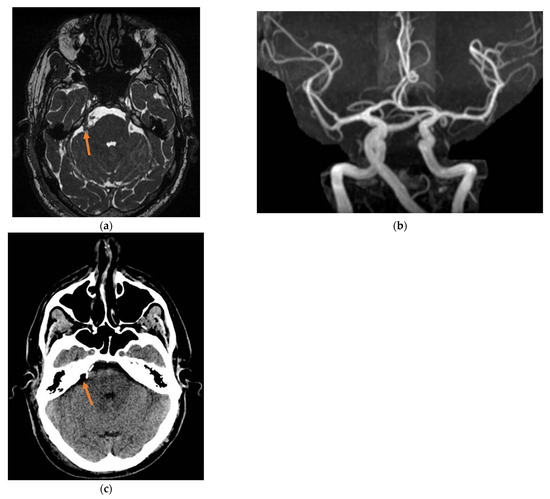

2. Case Presentation